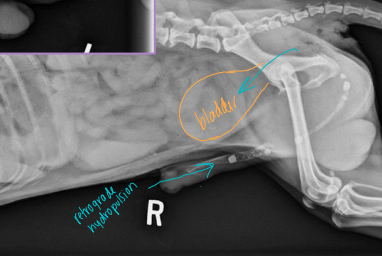

Dt: rectal exam, contrast rads, US

Tx: Sx (#1), Palliative: stool softeners, enemas, fiber

castration + herniorrhaphy: internal obturator flap, coccygeus of anal sphincter and sacrotuberous lig

stabilize bladder entrapment w/ catheterization/cystocentesis before Sx